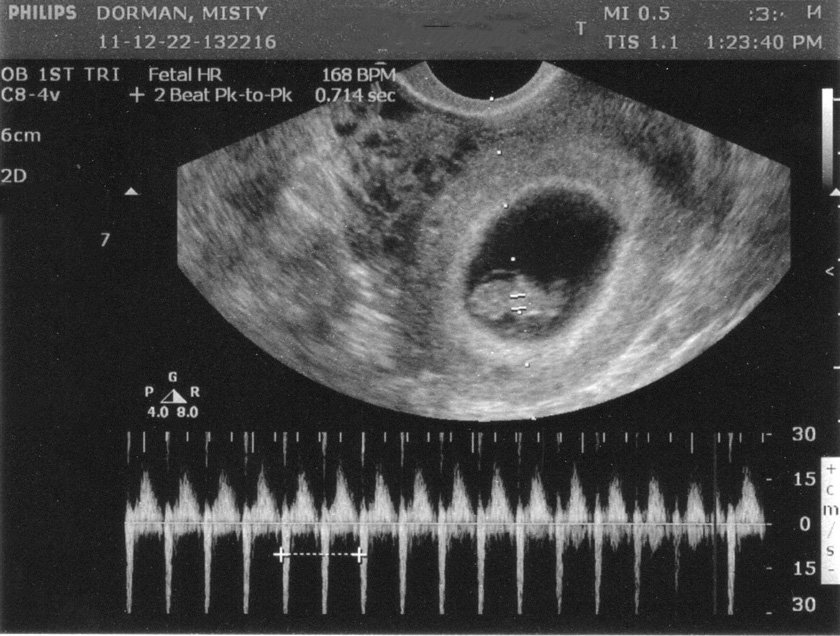

- Lồng ngực và tim thai: Lồng ngực của bào thai chứa tim thai, một cơ quan quan trọng trong hệ thống tuần hoàn của bào thai. Tim thai bắt đầu phát triển từ tuần thứ ba của thai kỳ và hoàn thiện vào khoảng tuần thứ tư. Tim thai có 4 buồng và hoạt động giống như tim người lớn, bơm máu đưa oxy và dinh dưỡng đến các bộ phận của cơ thể thai nhi.